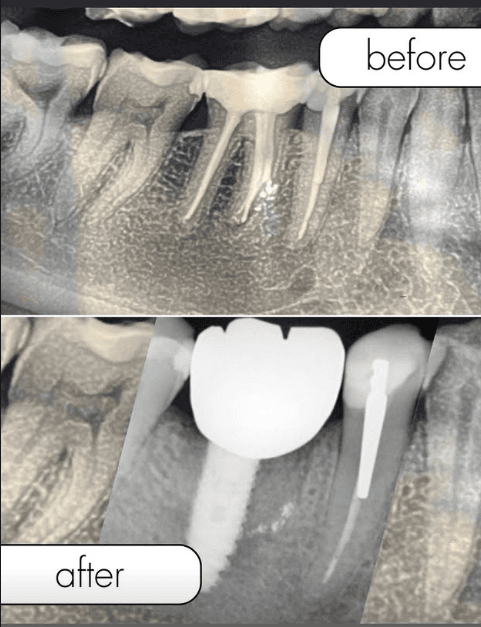

Before / After Results

Découvrez les transformations de nos patients